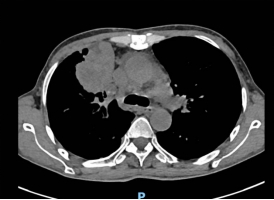

近日,一位肿瘤晚期的老年女性患者因并发急性心包填塞,被紧急送往广元市第一人民医院心胸血管外科就诊。入院时,患者已出现严重呼吸困难、心力衰竭等症状,剧烈的胸闷与濒死感让她痛苦不堪。检查显示,肿瘤转移引发的大量心包积液已对心脏形成致命压迫,若不及时解除压迫,患者随时可能因心跳骤停死亡,生命危在旦夕。

然而,患者处于肿瘤晚期,身体耐受度极差,还因年事已高合并多种基础疾病,给治疗带来了巨大挑战。传统治疗需采用全麻手术,需气管插管、机械通气辅助,不仅手术创伤大、术后并发症风险高,更可能因麻醉应激导致病情急剧恶化,甚至引发术中猝死。经综合评估,患者手术风险等级评估为极高危,传统治疗方案难以实施。

面对“治则风险极高、不治则即刻致命”的两难困境,市第一人民医院心胸血管外科副主任陈均带领团队迅速开展多学科会诊,结合患者病情特点与技术优势,果断决定采用Tubeless无管化胸腔镜心包开窗引流术。这一创新技术无需气管插管、无需留置导尿管,无需使用肌松剂,通过“三无”微创模式从根源上降低手术创伤与并发症风险,尤其适合老年体弱、危重疑难患者。

手术当天,陈均团队与麻醉科紧密协作。麻醉科张莉副主任、刘兴红医师在超声引导下精准区域神经阻滞,配合短效镇静镇痛药物,确保患者在自主呼吸状态下平稳接受手术。术中,陈均团队通过单孔胸腔镜精准定位心包积液区域,仅以微小切口完成开窗引流操作,快速排出压迫心脏的积液,成功解除了致命性心脏压迫。整个手术过程视野清晰、操作精准高效,在最大限度保障患者安全的同时,将手术创伤降至最低。